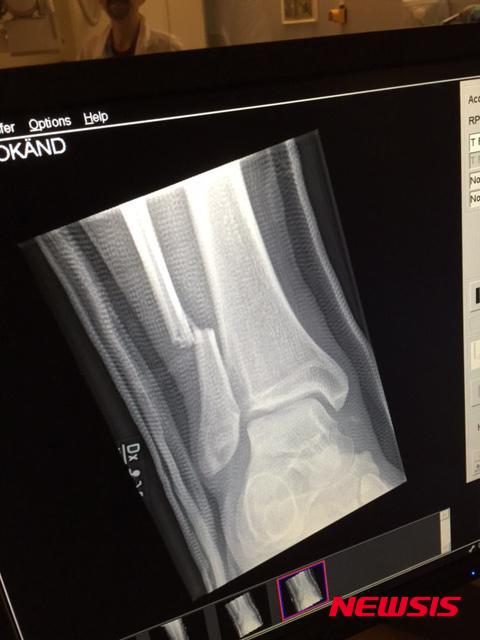

공연이 끝나 후 푸파이터스 트위터 계정에는 "고마워요. 예테보리, 놀라웠어요"(Thank you Gothenburg. That was amazing)라는 글과 함께 그롤 오른쪽 다리의 일부 뼈가 부러진 모습이 찍힌 X-레이 사진이 올라왔다.

'푸 파이터스' 데이브 그롤 오른쪽 다리 X-레이 사진(출처=푸파이터스 트위터)